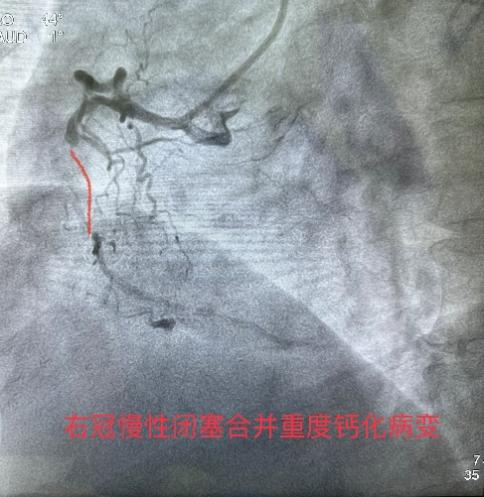

3月8日经过充分的术前准备,雷新军教授带领景林德博士和蔡安琪医生按照预定方案为患者实施了手术。冠脉造影示:RCA 2段慢性闭塞合并重度钙化,闭塞段长约30 mm,同向桥侧支供血使其远段显影(图3a);前降支散在斑块伴钙化,狭窄约25%-50%,并通过间隔支侧支循环向右冠逆向供血(图3b);回旋支11段狭窄约75%(图3c)。决定干预右冠:指引导管到位后在Guidezilla的支撑下,经Corsair微导管仔细操控GAIA 3rd穿过闭塞段进入远端血管真腔(图3d,e);然后通过微导管交换成旋磨导丝,使用1.5 mm Burr进行冠脉内斑块旋磨并抛光(图3f),造影见右冠恢复TIMI 3级前向血流,但2段残余狭窄最重处仍达90%(图3g);遂经导丝送入3.0*12 mm“Shockwave”冲击波球囊分段进行血管内碎石术:首先将压力充盈至4 atm后开始释放脉冲,松解钙化斑块,然后再将充盈压升至6 atm维持10秒,对靶病变进行低压球囊扩张成形(图3h);再次造影见右冠2段局限性夹层,闭塞段残余狭窄<10%(图3i),效果非常满意,遂由远及近衔接植入BioFreedom支架(图3j),历时约1小时手术成功,病人安返病房。

图3 经皮冠脉介入治疗